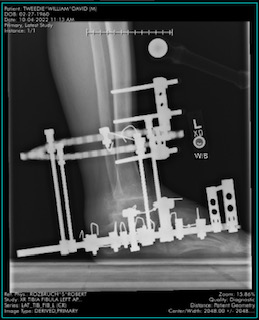

09/12/2022

8:00 AM

FUSION, ANKLE

EXCISION BONE-FIBULA

APPLICATION OF ILIZAROV/TAYLOR SPATIAL LOWER EXTREMITY

RELEASE TENDON LOWER EXTREMITY, FHL, FDL, PTT

RELEASE TARSAL TUNNEL

Rozbruch, S Robert

HSS MAIN OR

The above is a good example of what Dr. Rozbruch planned to do with my ankle and foot. I was really ready for my surgery!

The surgery took a couple of hours with general anesthesia used. I was rolled into the operation theater at 8am and when I awoke it was 7 pm! After the surgery, I was assigned a room at the HSS with a beautiful view!

I spent two nights at HSS in recovery. Pain was not an issue. I felt uncomfortable getting used to the new hardware placed on my foot and ankle, held by 15 rods and pins! HSS taught me how to get around using a walker and crutches. This was the beginning of the hardest part in my journey to walking again.